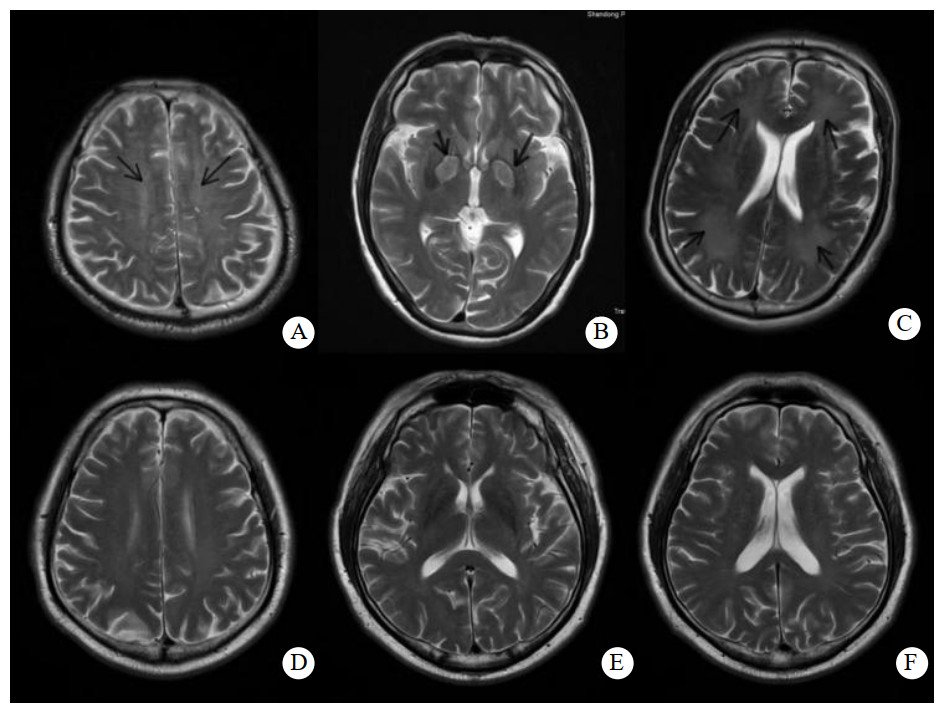

常规MRI中DEACMP表现为长T1、T2信号。DWI中DEACMP组与ACOP组相比,病变区域信号增强。见图 1。

| A为DEACMP半卵圆中心高信号改变;B为DEACMP苍白球高信号改变;C为DEACMP侧脑室周围高信号改变;D为Non-DEACMP组半卵圆中心低信号;E为Non-DEACMP组苍白球低信号;F为Non-DEACMP组侧脑室周围低信号 图 1 DEACMP组和ACOP组不同部位在ADC图中的表现 Fig 1 ADC images of different parts in DEACMP group and ACOP group |